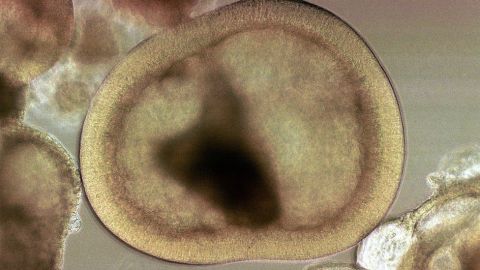

Muchas cosas se desconocen acerca de este tratamiento. Crédito: Getty Images

Hasta ahora, los investigadores se han centrado en desarrollar principalmente dos tipos diferentes de células madre: embrionarias y adultas.

Las células madre embrionarias, que se extraen de un embrión en crecimiento, tienen la ventaja natural de poder dar lugar a cualquier otra célula del cuerpo, un atributo conocido como pluripotencia.